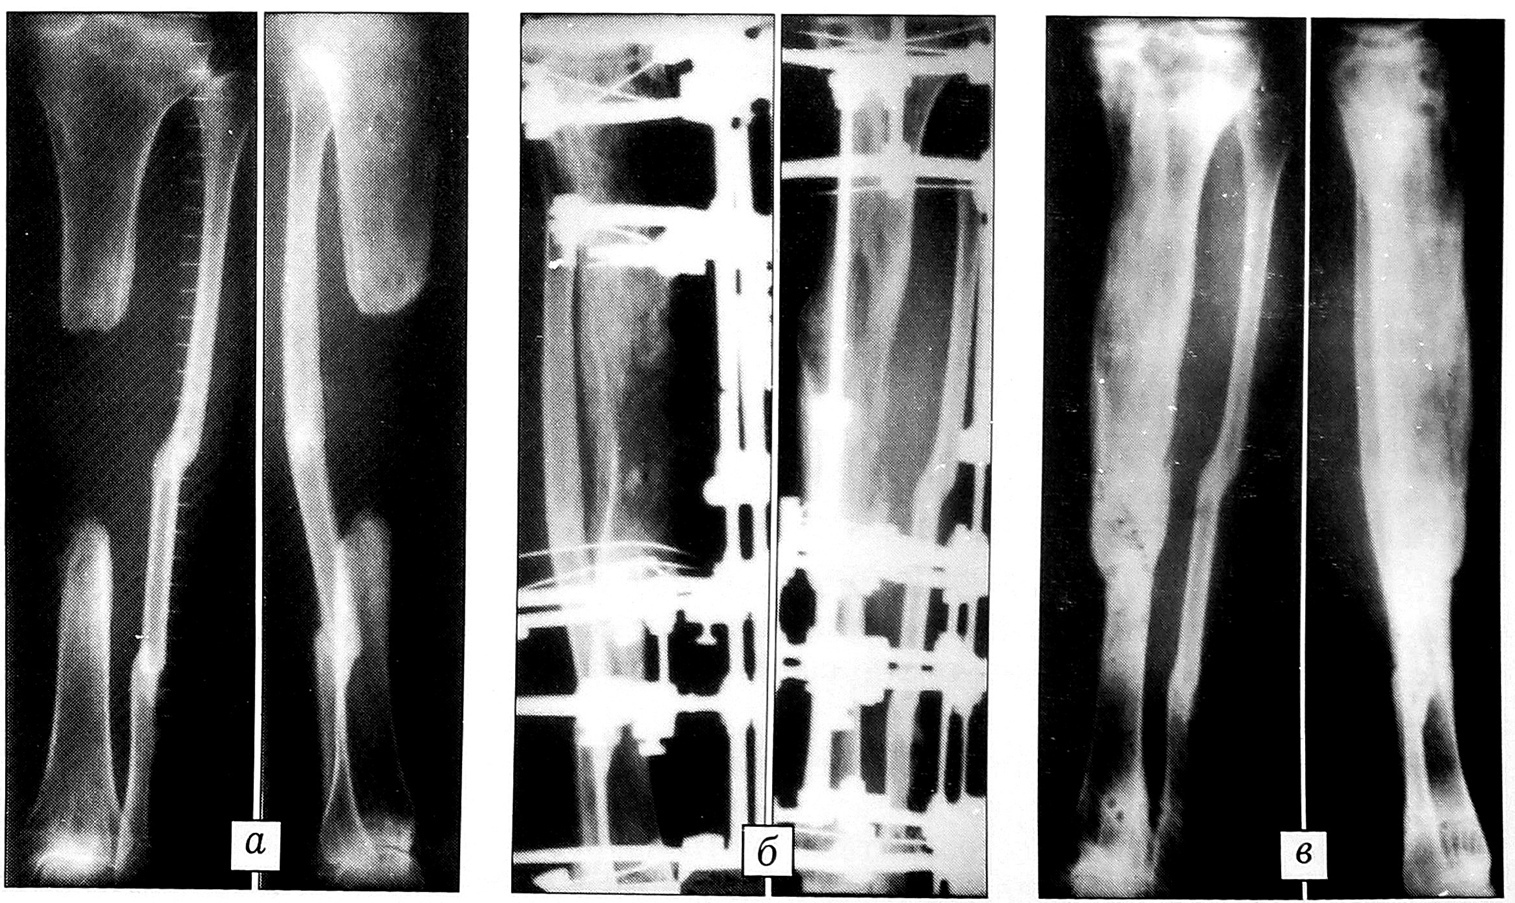

Больной М.,33 лет, поступил по поводу посттравматического дефект-диастаза левой большеберцовой кости 11 см. Укорочение сегмента 2 см. Рентгенологически определяются межотломковый диастаз 9 см, консолидированный двойной перелом левой малоберцовой кости с дублированием концов отломков (рис. 3). Межотломковый диастаз в условиях рубцового процесса возмещен одноуровневым удлинением проксимального отломка большеберцовой кости. Дистракция осуществлялась 176 дней, период последующей фиксации сегмента аппаратом продолжался 135 дней. Опороспособность голени восстановлена.

Рис. 3. Рентгенограммы больного М. 33 лет.a — до лечения; б — в процессе остеосинтеза; в — после снятия аппарата.